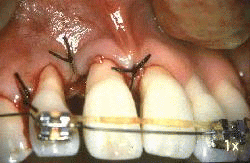

Mujer de 24 años de edad  que ha padecido  periodontitis juvenil desde los 16 años. Las lesiones periodontales se han tratado repetidamente durante los años precedentes y ella ha desarrollado una nueva  patología periodontal en el incisivo lateral derecho superior. Las profundidades de bolsa al sondaje de ese diente es de 4-10 mm  Un colgajo se ha levantado hasta la línea mucogingival y se ha expuesto el hueso maxilar. La pérdida de ligamento periodontal es severa en  mesial y distal  del lateral. En distal se observa un defecto óseo.

Otro colgajo se ha levantado en palatino. Se observa la pérdida del ligamento periodontal en  mesial y distal del lateral. Nótese el defecto óseo en forma de cráter en mesial del lateral.

Se realiza las suturas de los colgajos.  Note el cierre completo de los colgajos en interproximal.